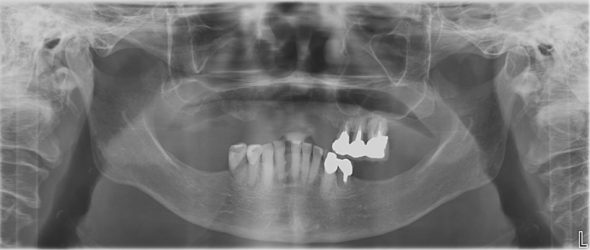

こちらはインプラントを埋入する前のレントゲンのお写真です。

写真は左右反転して見て下さい!